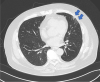

Results: Laryngoscopy revealed severe swelling of the transglottic region and exudates on the larynx. He was then diagnosed with COVID-19 and subjected to emergency tracheostomy for airway management. Until the emergence of the omicron variant, COVID-19 showed mainly lower airway and mild upper airway inflammatory features. However, upper airway stenosis should be suspected in cases presenting with "muffled speech," "dysphagia," "severe pain on swallowing," and "inspiratory dyspnea or stridor."